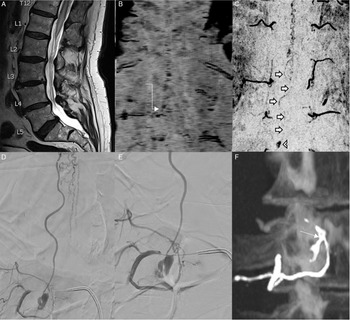

An 80-year-old male presented with a 3-month history of progressive right leg weakness and bilateral lower limb paresthesias. Examination at presentation showed right leg weakness (3/5 hip flexors, 4/5 knee extension, 4/5 foot dorsiflexion, and 4/5 foot plantar flexion), no bowel, or bladder dysfunction. An MRI of the spine demonstrated spinal cord edema extending from the mid-thoracic region to the conus, with serpiginous flow voids surrounding the lower cord and conus suggestive of a spinal dural arteriovenous fistula (SDAVF; Figure 1A). Time-resolved MRA was initially performed which suggested a SDAVF at the right L2 level (Figure 1B). At angiography, this level could not be catheterized due to focal aortic ectasia, and the SDAVF could not be identified. He underwent attempted surgical disconnection based on the MRI findings. Subsequent high-resolution MRA of the spine demonstrated a small venous pouch in the anterolateral epidural space at the right L3 level with persistent shunting to enlarged peri-medullary veins (Figure 1C). Diagnostic spinal angiogram was performed which demonstrated a spinal epidural arteriovenous fistula (SEAVF) with arterial supply from the right L2 and L3 segmental arteries, a large anterior epidural venous pouch and shunting to the perimedullary veins via a prominent radicular vein (Figure 1D/E) . Decision was made for endovascular embolization given the difficulties encountered with finding such fistulae on open surgical approach. Embolization was performed from the right L3 segmental level with Squid 12 EVOH copolymer liquid embolic (Balt Extrusion, Montmorency, France). Penetration of the fistula network including the epidural pouch was achieved, as well as the distal aspect of the L2 segmental artery via reflux. Subsequent angiographic runs demonstrated no persistent fistula. Follow-up unenhanced CT demonstrates the liquid embolic cast highlighting the SEAVF anatomy (Figure 1F) . The patient was discharged without complication.

Figure. 1. Sagittal T2 images (A) of the lumbar spine demonstrates lower cord and conus edema. Time resolved MRA (B) suggests a possible spinal dural arteriovenous fistula at the right L2 level (white elbow arrow). Post-surgery high resolution MRA (C) demonstrates a persistent fistula, and a small ventral venous pouch is seen at the right L3 level (white arrow head) with a vein coursing towards to conus (white short arrows), suggesting the presence of a spinal epidural arteriovenous fistula (SEAVF). Repeat angiography (D,E) demonstrates a SEAVF with a ventral venous pouch at the right L3 level with arterial supply from the right segmental L3 (and L2) segmental arteries, and shunting to peri-medullary veins. Post-embolization CT (F), shows the cast of the liquid embolic highlighting the disconnected fistula(white arrow) with the epidural venous pouch.